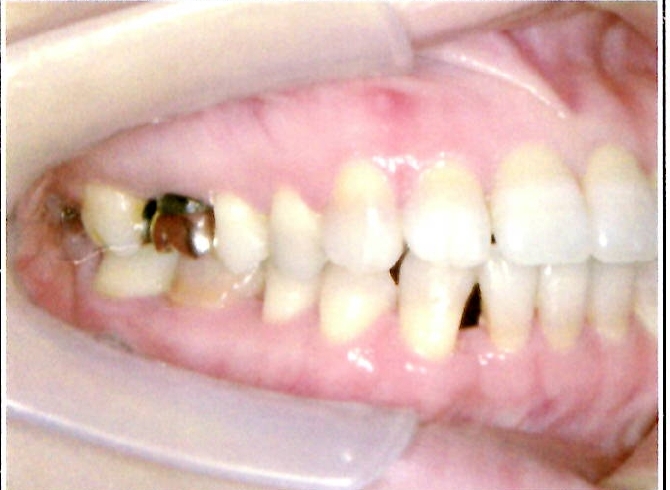

| 主訴・治療前の状態 | 著しい叢生(歯並びのガタガタ)があり、また6歳臼歯(第一大臼歯)が破折していた状態でした。 |

| 治療内容 | 通常の抜歯矯正では第一小臼歯(4番)を抜歯することが多く、その方が治療期間を短縮できますが、小川さんの場合は破折していた6歳臼歯を抜歯し、そのスペースを活用して歯列を整えました。これにより、健康な歯の本数を維持しながら矯正治療を行うことができました。 |

| 治療結果 | 治療前と比較して歯並びが大きく改善し、見た目も大幅に良くなりました。患者様にも大変喜んでいただけた症例です。 |